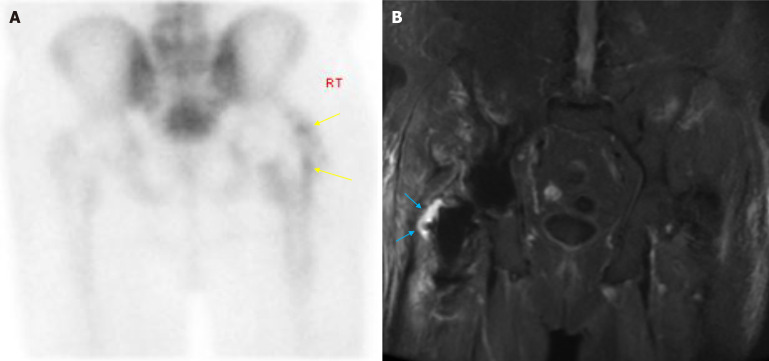

Abstract Image